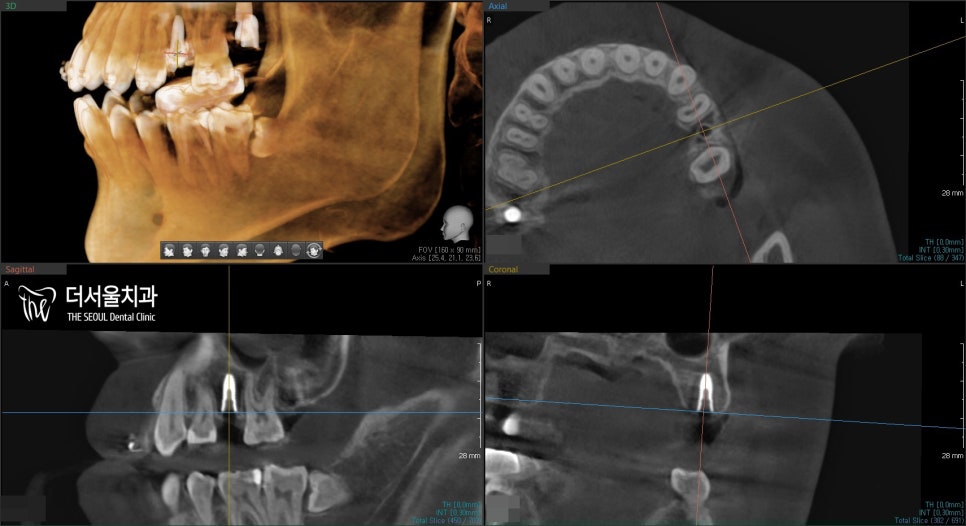

CBCT 촬영을 통해

올바른 위치에 잘 식립되었는지

한 번 더 체크를 해줬구요.

올바르게 잘 식립되었네요. ^^